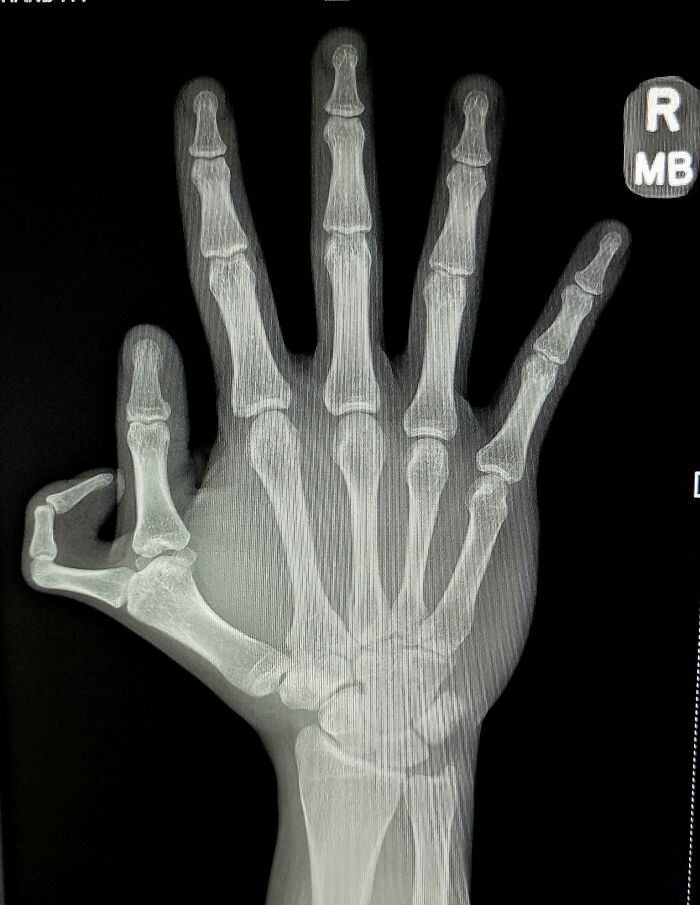

Loss Of Blood Flow To My Fingers Due To Raynaud’s Disease

My mom had it. I have it. It's very painful. I need to be very careful and very fast if I'm shopping in the freezer section. No rifling through to check things out. See what you want. Grab it and throw it in the basket very quickly. Even then, the ends of my fingers turn white and hurt for a number of minutes. I wear warm gloves, even in the early fall to late spring. If very severe you can actually need to have fingers or toes amputated due to lack of blood flow.